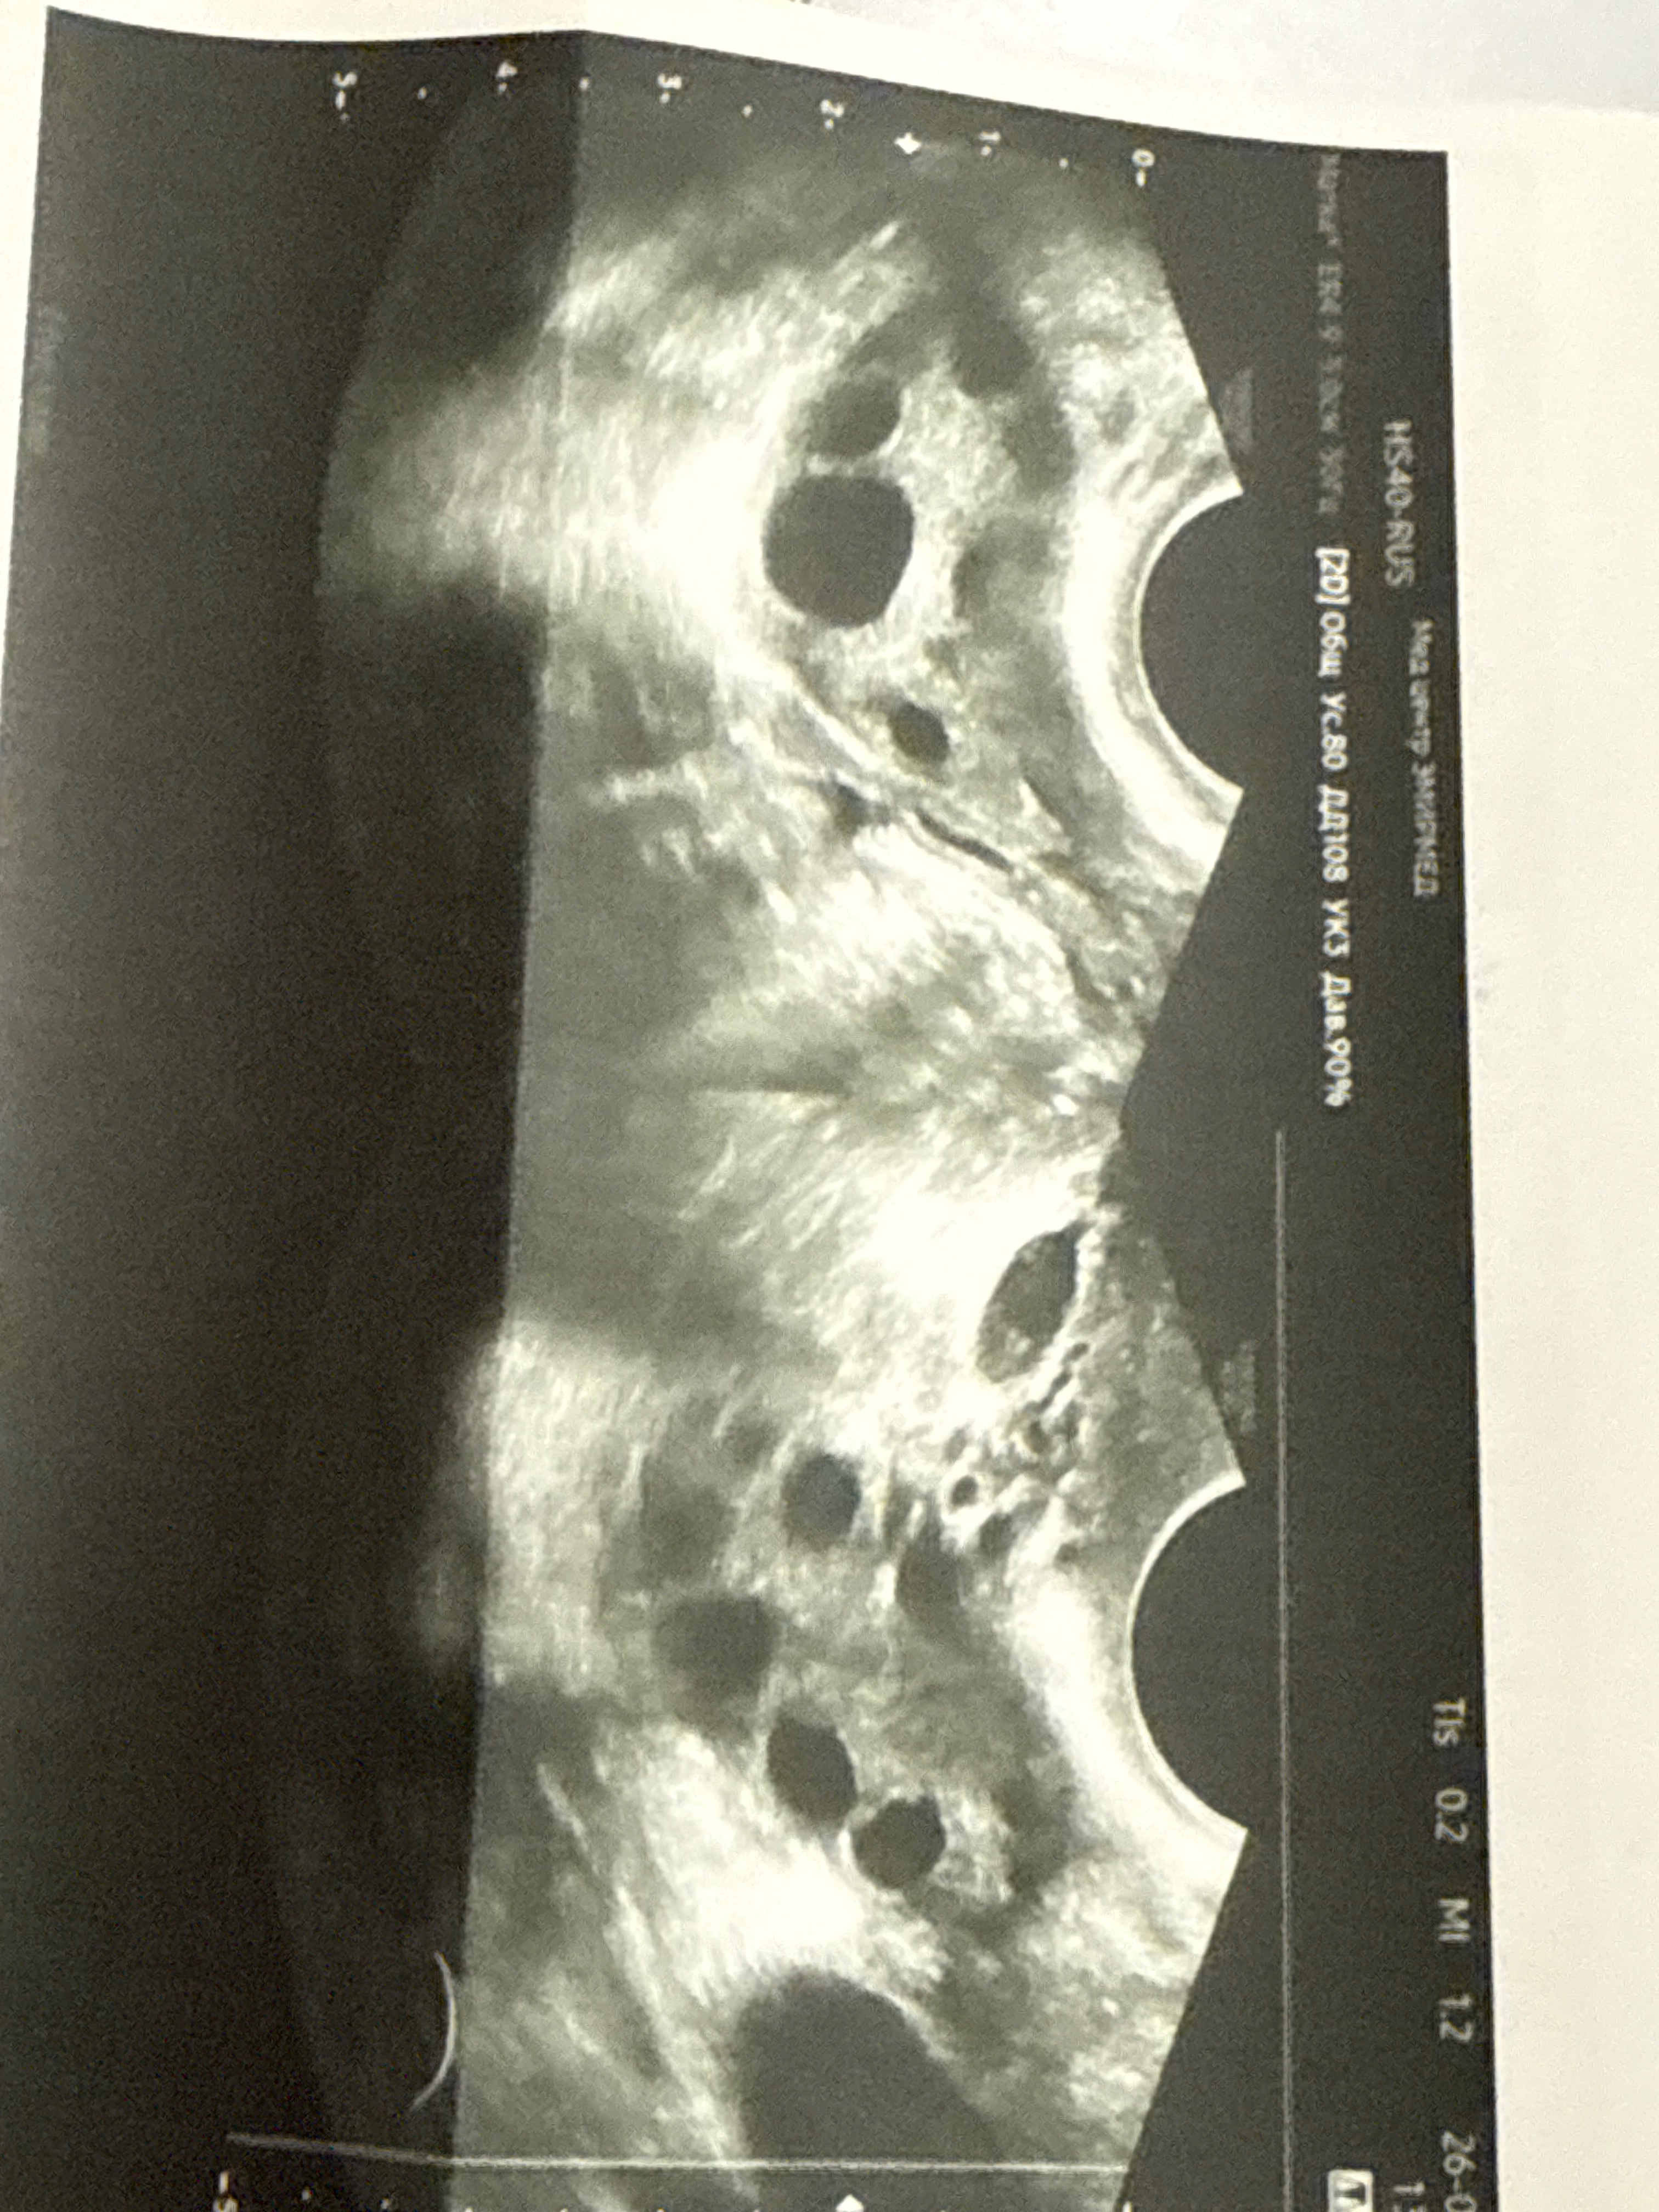

сходила на узи - крохотный для 11ДЦ фолликул 10мм и огромное сумасшедшее количество маленьких фолликул.

Эндометрий радует, соответствует циклу.